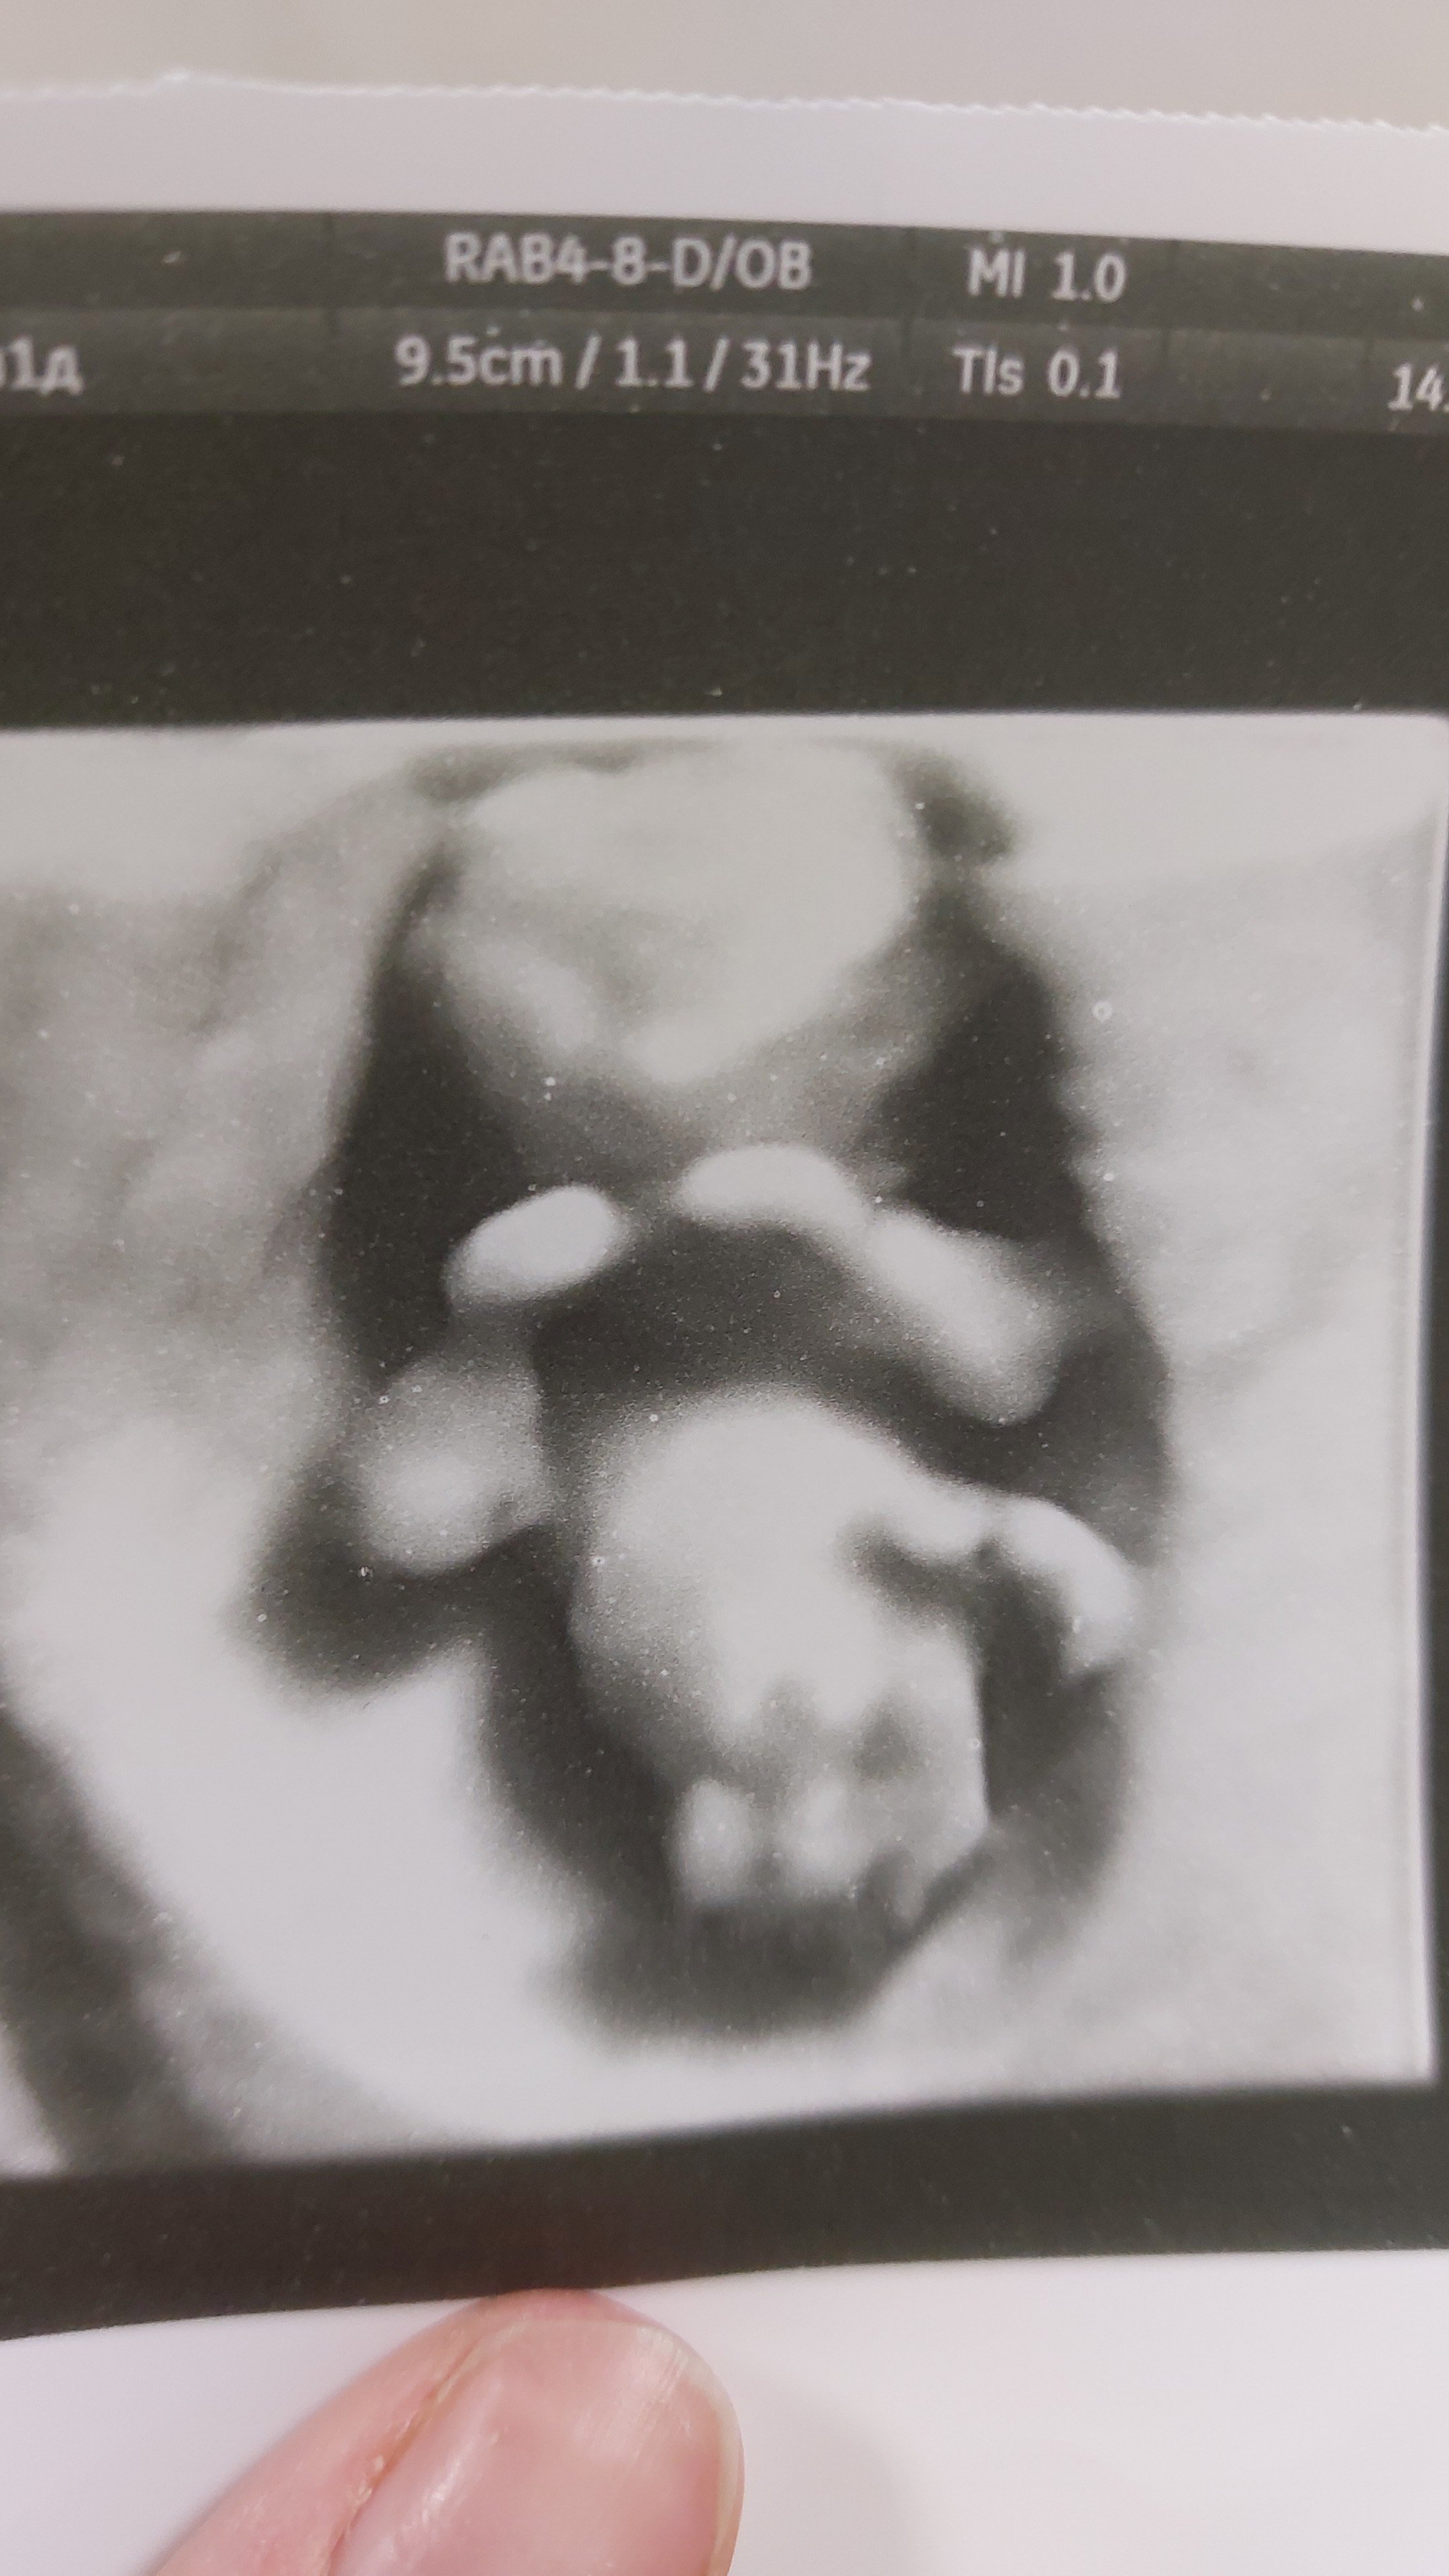

Konu Hakkında Merhaba, tarihinde Gebelikle ilgili Sorum Var kategorisinde Ulduz.kiz anesi👶❤ tarafından oluşturulan Bakarmisiz canlarim💜 başlıklı konuyu okuyorsunuz. Bu konu şimdiye dek 1,237 kez görüntülenmiş, 12 yorum ve 1 tepki puanı almıştır...

Konbuyu başlatan Ulduz.kiz anesi👶❤